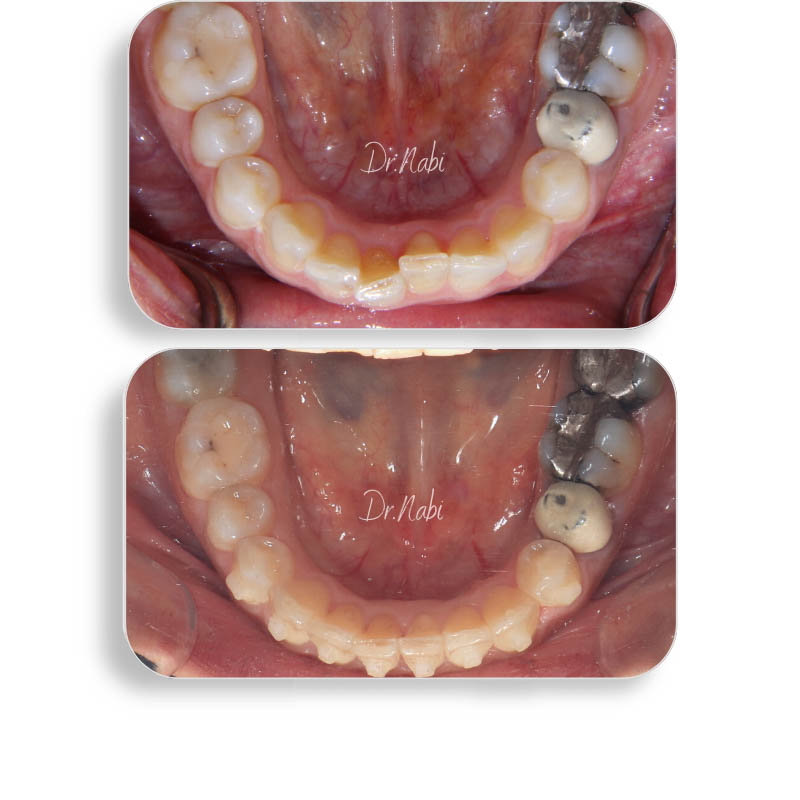

بیمار خانم 37 ساله که به جهت اصلاح نامرتبی فک پایین مراجعه کردند. در حدود 10 ماه با ارتودنسی نامرئی تمامی نامرتبی ها اصلاح شد.

اصلاح نامرتبی فک پایین

: ارتودنسی نامرئی